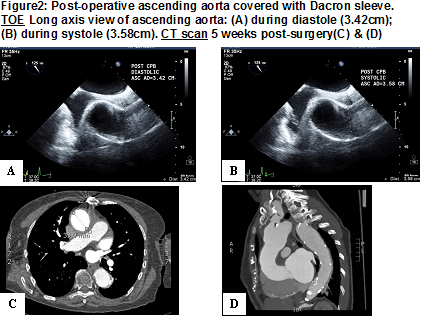

71 minutes on cardiopulmonary bypass and 39 minutes in cross-clamp time was required to achieve a nice and smooth sleeve around 7 cm dilated ascending aorta. Post cardiopulmonary bypass trans-esophageal echocardiogram confirmed a smooth and wrinkle free reduction of ascending aorta diameter, without aortic regurgitation with the following measurements:

The patient had CT angiogram aorta (Figure 2C & 2D) five weeks post-surgery, which was reported as "satisfactory appearance of the ascending aortic replacement." The radiologist could not differentiate that this patient had sleeve around ascending aorta not replacement. The ascending aorta measures a maximum diameter of 3.9 mm.